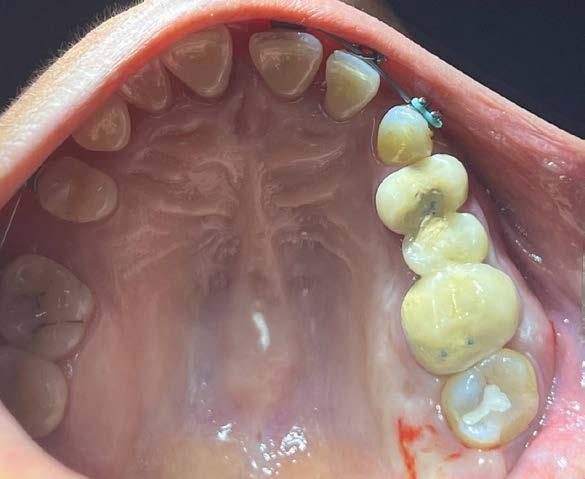

Caso clínico

Paciente femenino de 49 años de edad la cual acude a la consulta por odontalgia en segundo molar superior derecho, presenta obturación temporal y ausencia clínica de tercer molar superior

derecho (Figura 1). Especialista en endodoncia solicita cone beam en donde se visualiza lesión periapical extensa que involucra segundo y tercer molar ipsilateral y engrosamiento de la mucosa del seno maxilar sugerente de sinusitis maxilar crónica y su cercanía

con el tercer molar de dicha estructura (Figura 2).

Como antecedentes de importancia, la paciente refiere tratamiento previo por otorrinolaringología sin mejoría alguna, presentando rinorrea y obstrucción nasal constante ocasionando hiposmia, pero no correlacionándolo con una causa de origen dental.

Por lo que se propone procedimiento quirúrgico con la evidente comunicación oroantral al realizar las extracciones de los órganos dentales involucrados. Previa asepsia y antisepsia, colocación de campos estériles, extracción de segundo y tercer molar superior derecho e incisión envolvente con descarga mesial (Figura 3), rotación y afronte mediante puntos simples de la bola adiposa de Bichat para el cierre de la comunicación oroantral (Figura 4), farmacoterapia con base en amoxicilina con ácido clavulánico. Una semana después refiere no presentar rinorrea y mejoría al 100% de la obstrucción. Posterior a 6 meses de evolución clínica (Figura 5) y radiográficamente (Figura 6), no se observa comunicación oroantral o paso de líquidos de la cavidad oral a la cavidad nasal.

Figura 1. Fotografía oclusal.